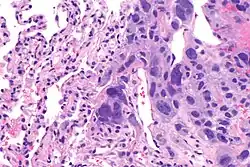

Choriocarcinoma

Choriocarcinomas are exceptionally rare which account for 2.1%-3.4% of all OGCTs.[10] Under gross examination, the syncytiotrophoblast cells are aligned in a plexiform arrangement with the mononucleated cytotrophoblast cells surrounding the foci of the hemorrhage.[1] Choriocarcinomas can be divided into gestational choriocarcinomas and non-gestational choriocarcinomas which have immunohistochemical differences.[11]